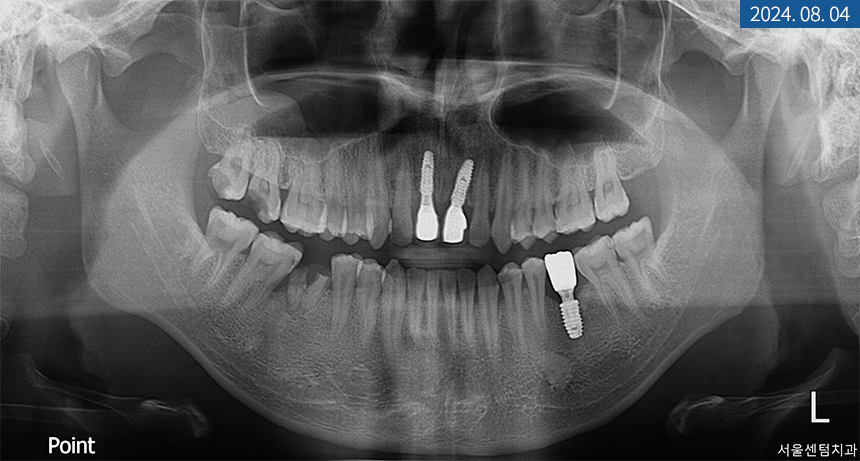

먼저 상악 #21번 어금니 발치를 진행하기로 했고

발치 후 기존 영구치 방향을 따라

인공 치근을 심은 후

필요시 GBR 골 이식재를 넣고

차폐막으로 덮기로 했습니다.

골 유착이 되는 동안에는

좌측 하악 어금니에 픽스처를 식립하고

전체 치주 질환을 개선하면서

경과를 관찰하기로 했습니다.

또, 좌측이 완성된 후에는

우측 앞니에 임플란트를 식립해서

마무리하기로 했고요.

#21번을 진행하면서

하악 대구치도 픽스처 식립을 했는데요.

이 부분은 치조골 상태가 양호해서

바로 힐링 어버트먼트까지 체결해 드렸습니다.